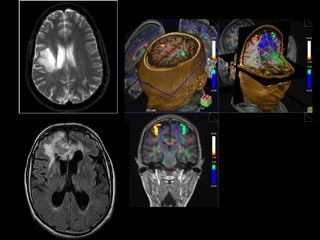

Imagem ponderada em T1

Imagem ponderada em T2

Contraste paramagnético

APARELHO DE RESONÂNCIA MAGNÉTICA

3 Teslas = 60.000 x campo magnético da Terra!